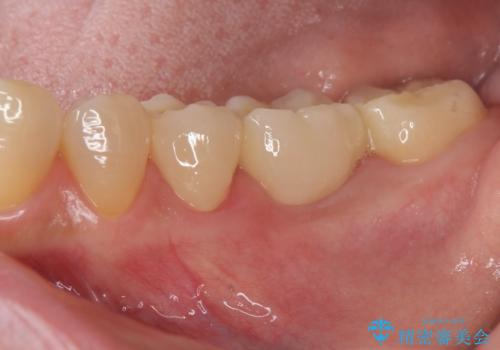

[ジルコニアクラウン] 前歯をきれいに

- 幼少時に行った前歯の治療、経年的に劣化し審美面の改善を求めて来院されました。

長期的な予後を見込むために、根管治療のやり直しから計画します。

- 13万円(仮歯・ファイバーコア・ジルコニアクラウン)費用は治療当時の料金となります

ジルコニアクラウンは色調を合わせることができるため、周囲の歯の色に調和し審美的な仕上がりを期待することができます。